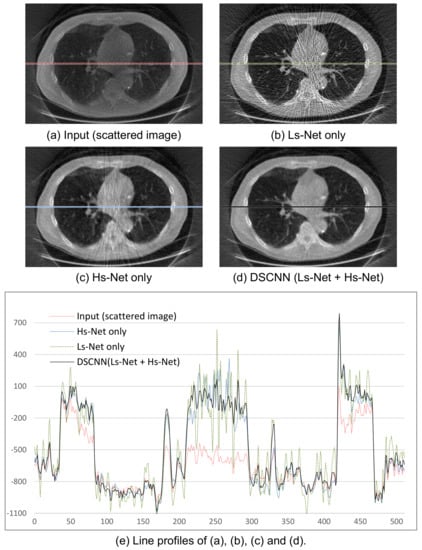

The average SSIM of 0.992 in Table 3 indicates that the proposed method can produce the scatter correction with high structural similarity with small variance. This is a required property of scatter correction, because a result with less scatter could provide additional artifacts or lose important information for medical diagnosis. Figure 8a–d shows the visual results of the two correction methods, and Figure 8e the line profiles of the four images in Figure 8a–d. Again, the proposed method predicts the target images more accurately than the MC-based one.

The performances of the 3D reconstructed image after scatter correction are shown in Figure 9. The images in Figure 9b–d were obtained from the separately trained Ls-Net and Hs-Net, and from the combined Ls- and Hs-Net, respectively. Figure 9b shows that a single branch of Ls-Net enhances the overall contrast of the image by compensating for the low-frequency scatter component, but generates streak artifacts due to high-frequency component of scatter and noise. Meanwhile, Figure 9c shows that a single branch of Hs-Net reduces the streak artifacts, but the corresponding profile in Figure 9e reveals the uniformity of the image is not so good. Further, relatively numerous artifacts are visibly, especially on the pathway of the X-ray beam going through thick and dense objects where severe scatter occurs. In summary, Ls-Net is suitable for correcting the low-frequency scatter component, but not the high-frequency component. Therefore, the dual-branch structure, where Hs-Net complements Ls-Net, effectively provides scatter correction, as shown in Figure 9d. Figure 9e shows the profile images of a specific line of the resulting images.